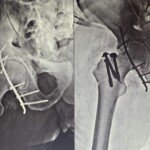

Dr. Tripathi specializes in the intricate field of pelvic and acetabular surgery, a branch of orthopedics dealing with complex fractures and injuries of the pelvic girdle and hip socket. His extensive training and experience enable him to handle the most challenging cases with precision and care. He is adept at both surgical and non-surgical management of these conditions, ensuring comprehensive care tailored to each patient’s needs.